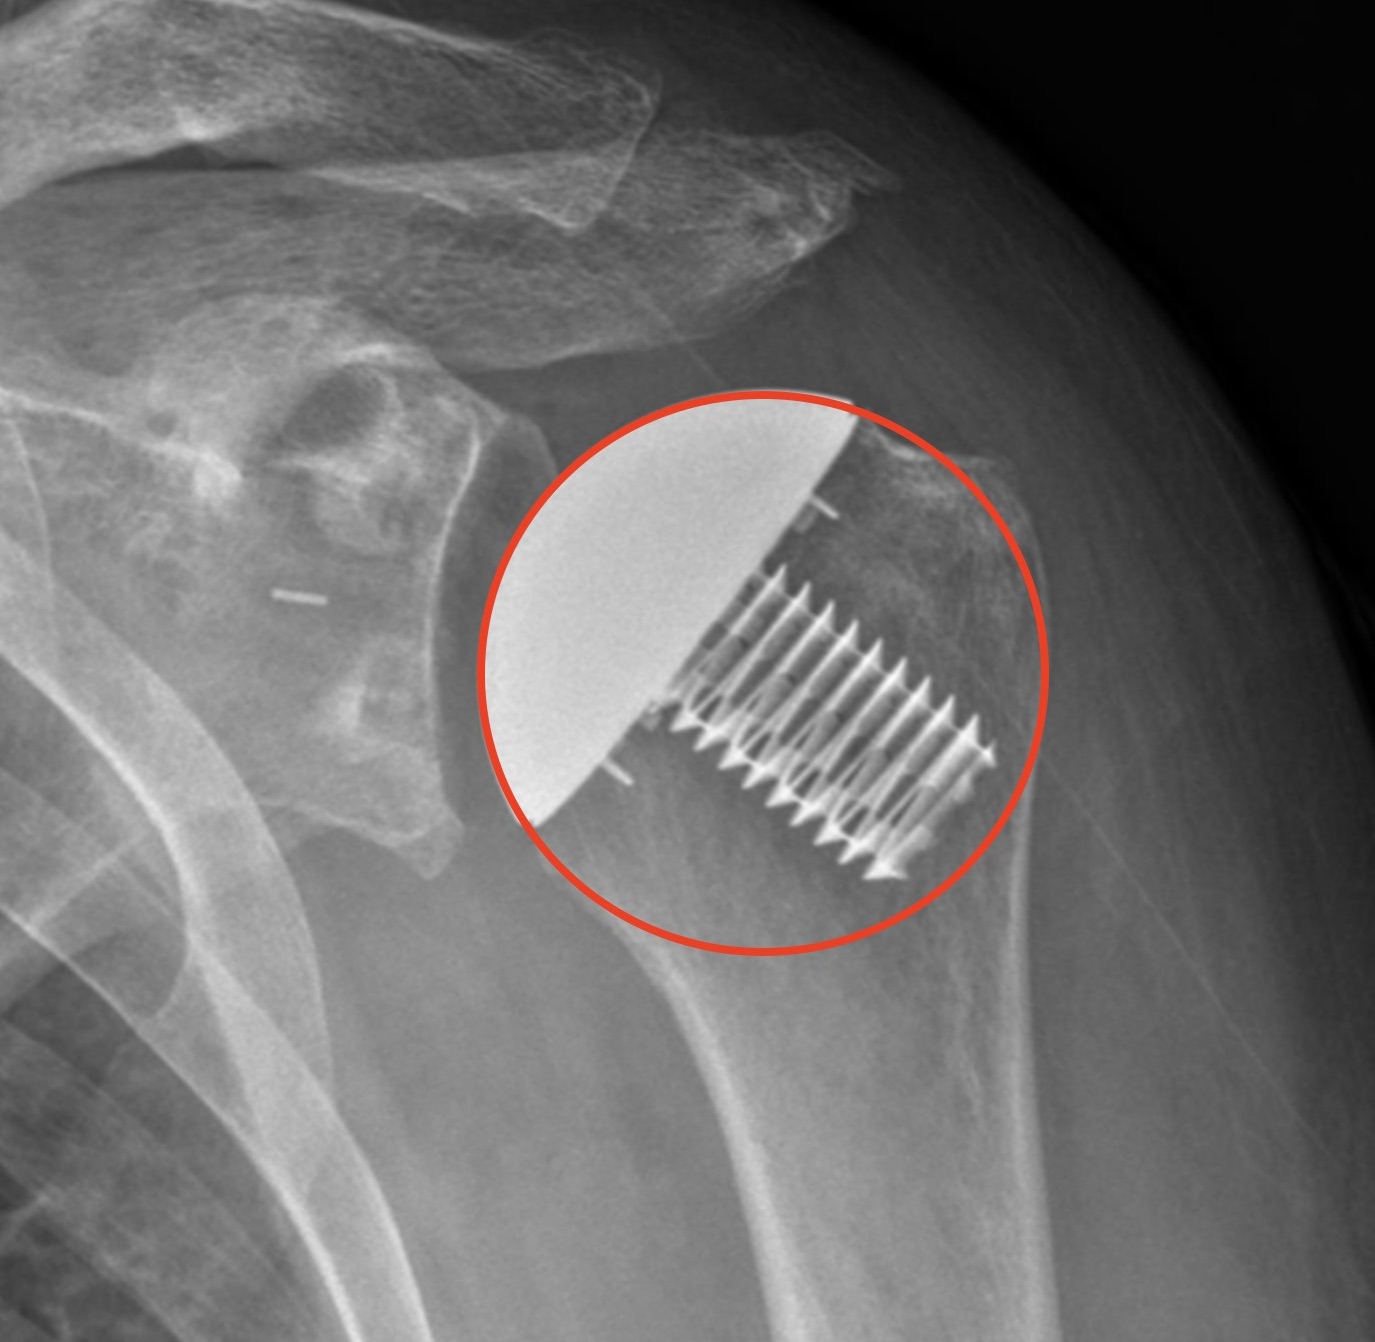

Physical Therapy and Reverse Shoulder Arthroplasty – Acromial Fracture

Acromial fracture after reverse shoulder might be related to early formal physical therapy Continue reading

COR and the Iannotti circle

“A high position of the humeral component relative to the greater tuberosity was the most common problem with humeral component positioning” Franta, Lenters, Mounce, Neradilek, Matsen “SAFE” study JSES 2007 Glenoid side Shoulder surgeons have recognized the importance of glenoid component positioning in outcomes of anatomic shoulder arthroplasty. Many surgeons have bolstered their academic prowess… Continue reading